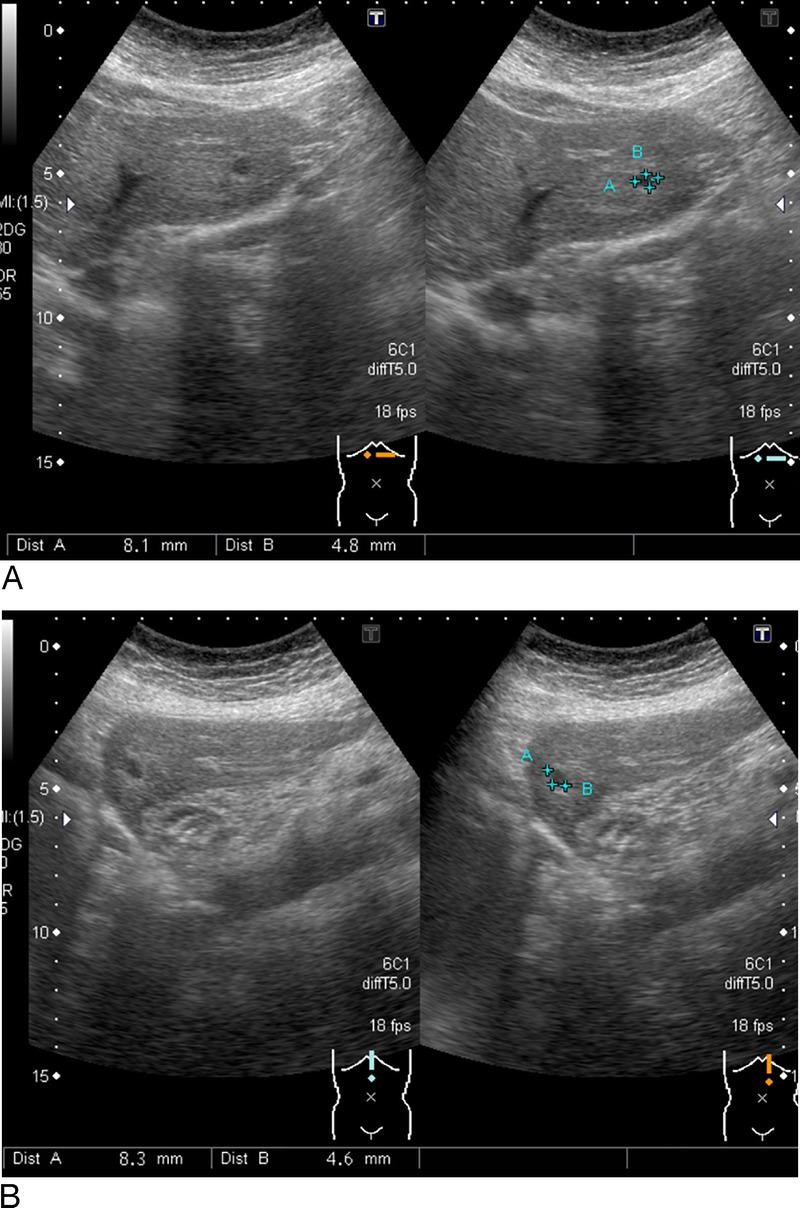

A suspected case of hepatic reactive lymphoid hyperplasia in which EUS-fine needle aspiration contributed to the diagnosis.

Endosc Ultrasound. 2024 Nov-Dec;13(6):379-381. doi: 10.1097/eus.0000000000000092. Epub 2024 Dec 30.